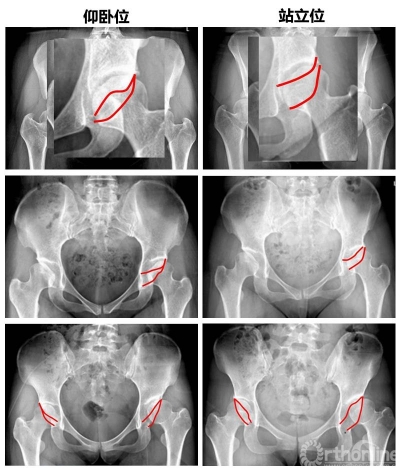

图1. 骨盆的三维位置变化

随着人类祖先从四肢行走变成直立行走,骨盆也逐渐朝着适应站立位的方向进化。站立与行走是人体功能位,站立位也更能体现骨盆和髋臼周围肌肉和矢状面平衡和动态变化。但一般诊断时患者普遍以仰卧位姿势行X线片,这样获得的患者骨盆信息是否与站立时存在差异?

对了研究从仰卧位到站立位骨盆变化,张教授和团队对照了110例接受髋臼周围截骨(PAO)手术的发育性髋关节发育不良(DDH)患者[男性:32例(52hips),女性:78例(135hips)],与36名正常对照者在仰卧位和站立位的骨盆前后X线片。

图2 仰卧位与站立位髋臼前倾角变化

结果发现,骨盆从仰卧位到站立位,PSSC减小,骨盆后倾,髋臼前倾角增大,髋臼前覆盖减小。而对于DDH患者,为消除前侧不稳定,骨盆会发生代偿性前倾。因此DDH患者站立位时骨盆较正常人前倾增大。